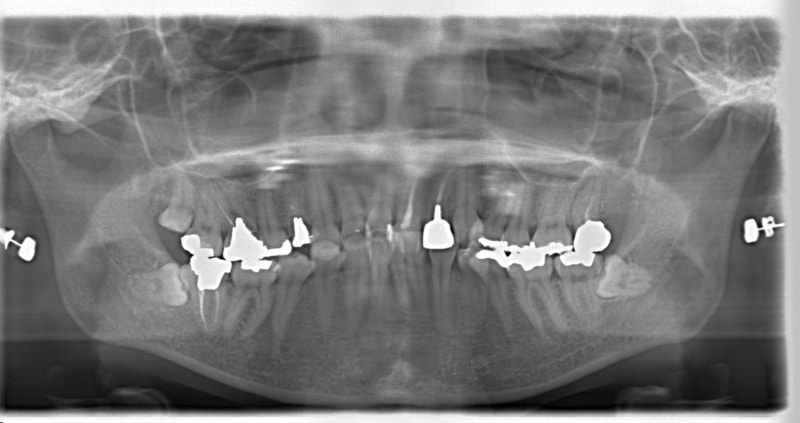

治療前

治療開始時